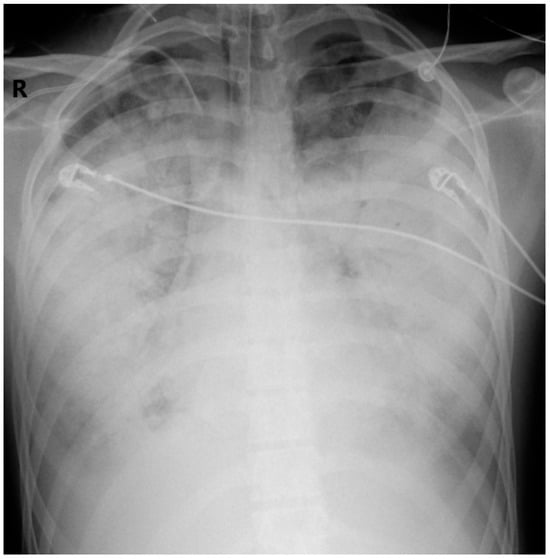

2.3. Case Evolution